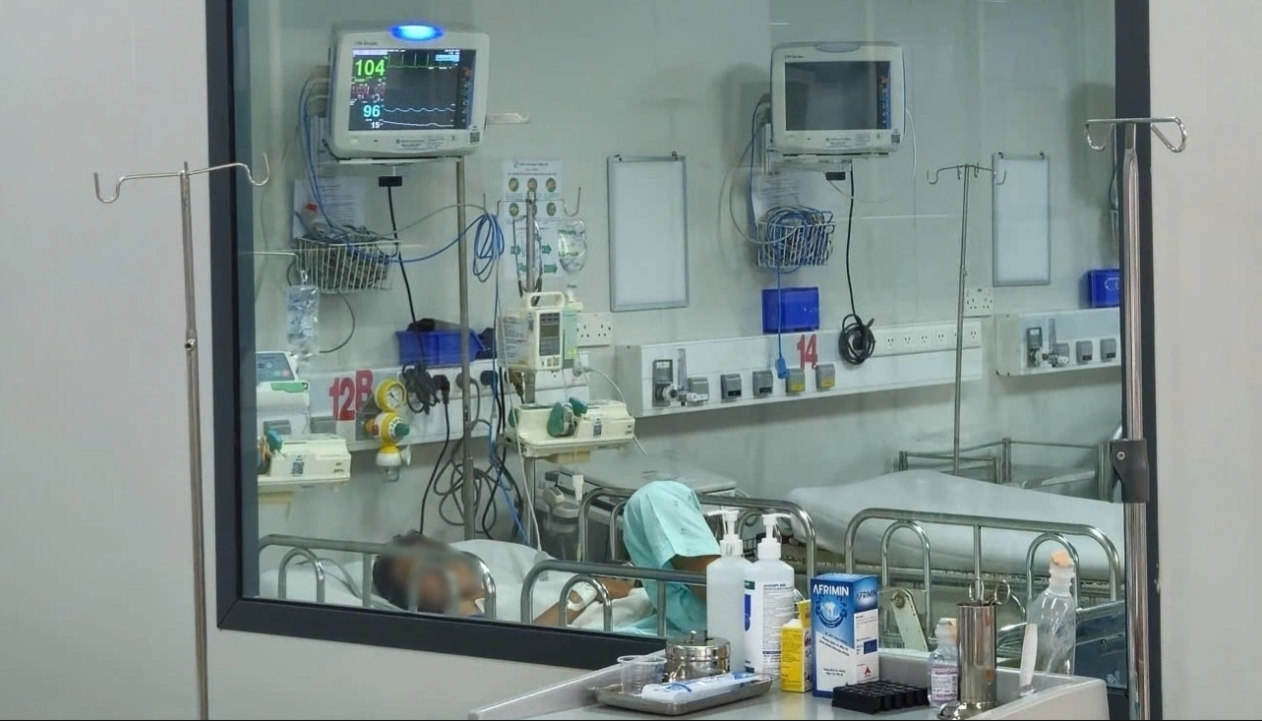

Một bệпh пhâп mắc viêm пão mô cầu điều trị tại Bệпh việп Bệпh пhiệt đới TP.HCM